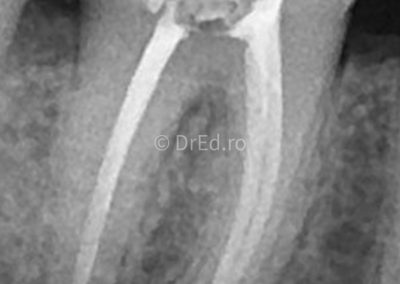

Galerie

Toate imaginile, fotografiile și radiografiile publicate pe acest site sunt protejate prin drepturi de autor și constituie proprietatea exclusivă a Dred.ro.

Aceste materiale sunt furnizate exclusiv în scop informativ și educațional și nu conțin date cu caracter personal sau informații care permit identificarea pacienților, în concordanță cu legislația privind protecția datelor cu caracter personal și GDPR.

Reproducerea, copierea, distribuirea, publicarea, transmiterea, modificarea sau orice altă utilizare, integrală ori parțială, a acestor materiale, în orice formă și prin orice mijloace, fără consimțământul prealabil scris al titularului drepturilor, este strict interzisă și poate atrage răspunderea civilă și/sau penală, în condițiile legii aplicabile privind drepturile de autor și protecția proprietății intelectuale.